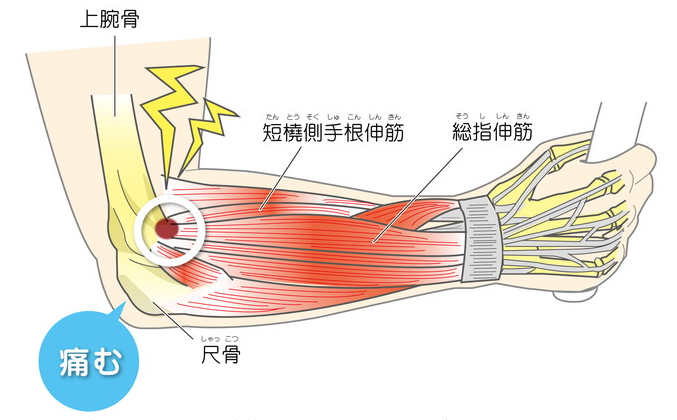

テニス肘とは

上腕骨外側上顆炎とは、肘の外側に痛みが現れる疾患で、スポーツのなかではテニスに関連する疾患であることから、「テニス肘」と呼ばれることもあります。ものを持ち上げたり、手をひねったりする動作を繰り返すことを原因として発症します。

なぜあなたのテニス肘が今まで改善しなかったのか?

身体全体のバランスをみず肘にしかアプローチしていなから

肘が痛いから肘の治療しかしない

これらの処置は”テニス肘”の原因の一つである筋肉を緩め、神経と血管の圧迫を取り除くという目的でおこなわれ”テニス肘”に非常に有効です。

しかし、これでも改善しない”テニス肘”はどうすればよいのでしょうか?

実は上記のような施術を受けても”テニス肘”が改善されない場合に

2つのことが考えられます。

1.肘周辺の筋肉がうまくとれてない/span>

2上半身のほかに原因がある

1.は単純に

施術を施す筋肉は深い筋肉がとれてない

日常生活などですぐ肘の筋肉が固くなる

などが考えられます。

2.に関しては、

”テニス肘”は肘以外に”腕、背中、首 肩といった部分の施術が必要になるケースがあります。

腕や背中や首、肩の問題を見落としている整骨院(接骨院)も非常に多いのです。

ではなぜ当院の施術で”テニス肘”が改善するのか?

肘周囲の筋肉はもちろん、腕、背中、首、肩までも調整するから